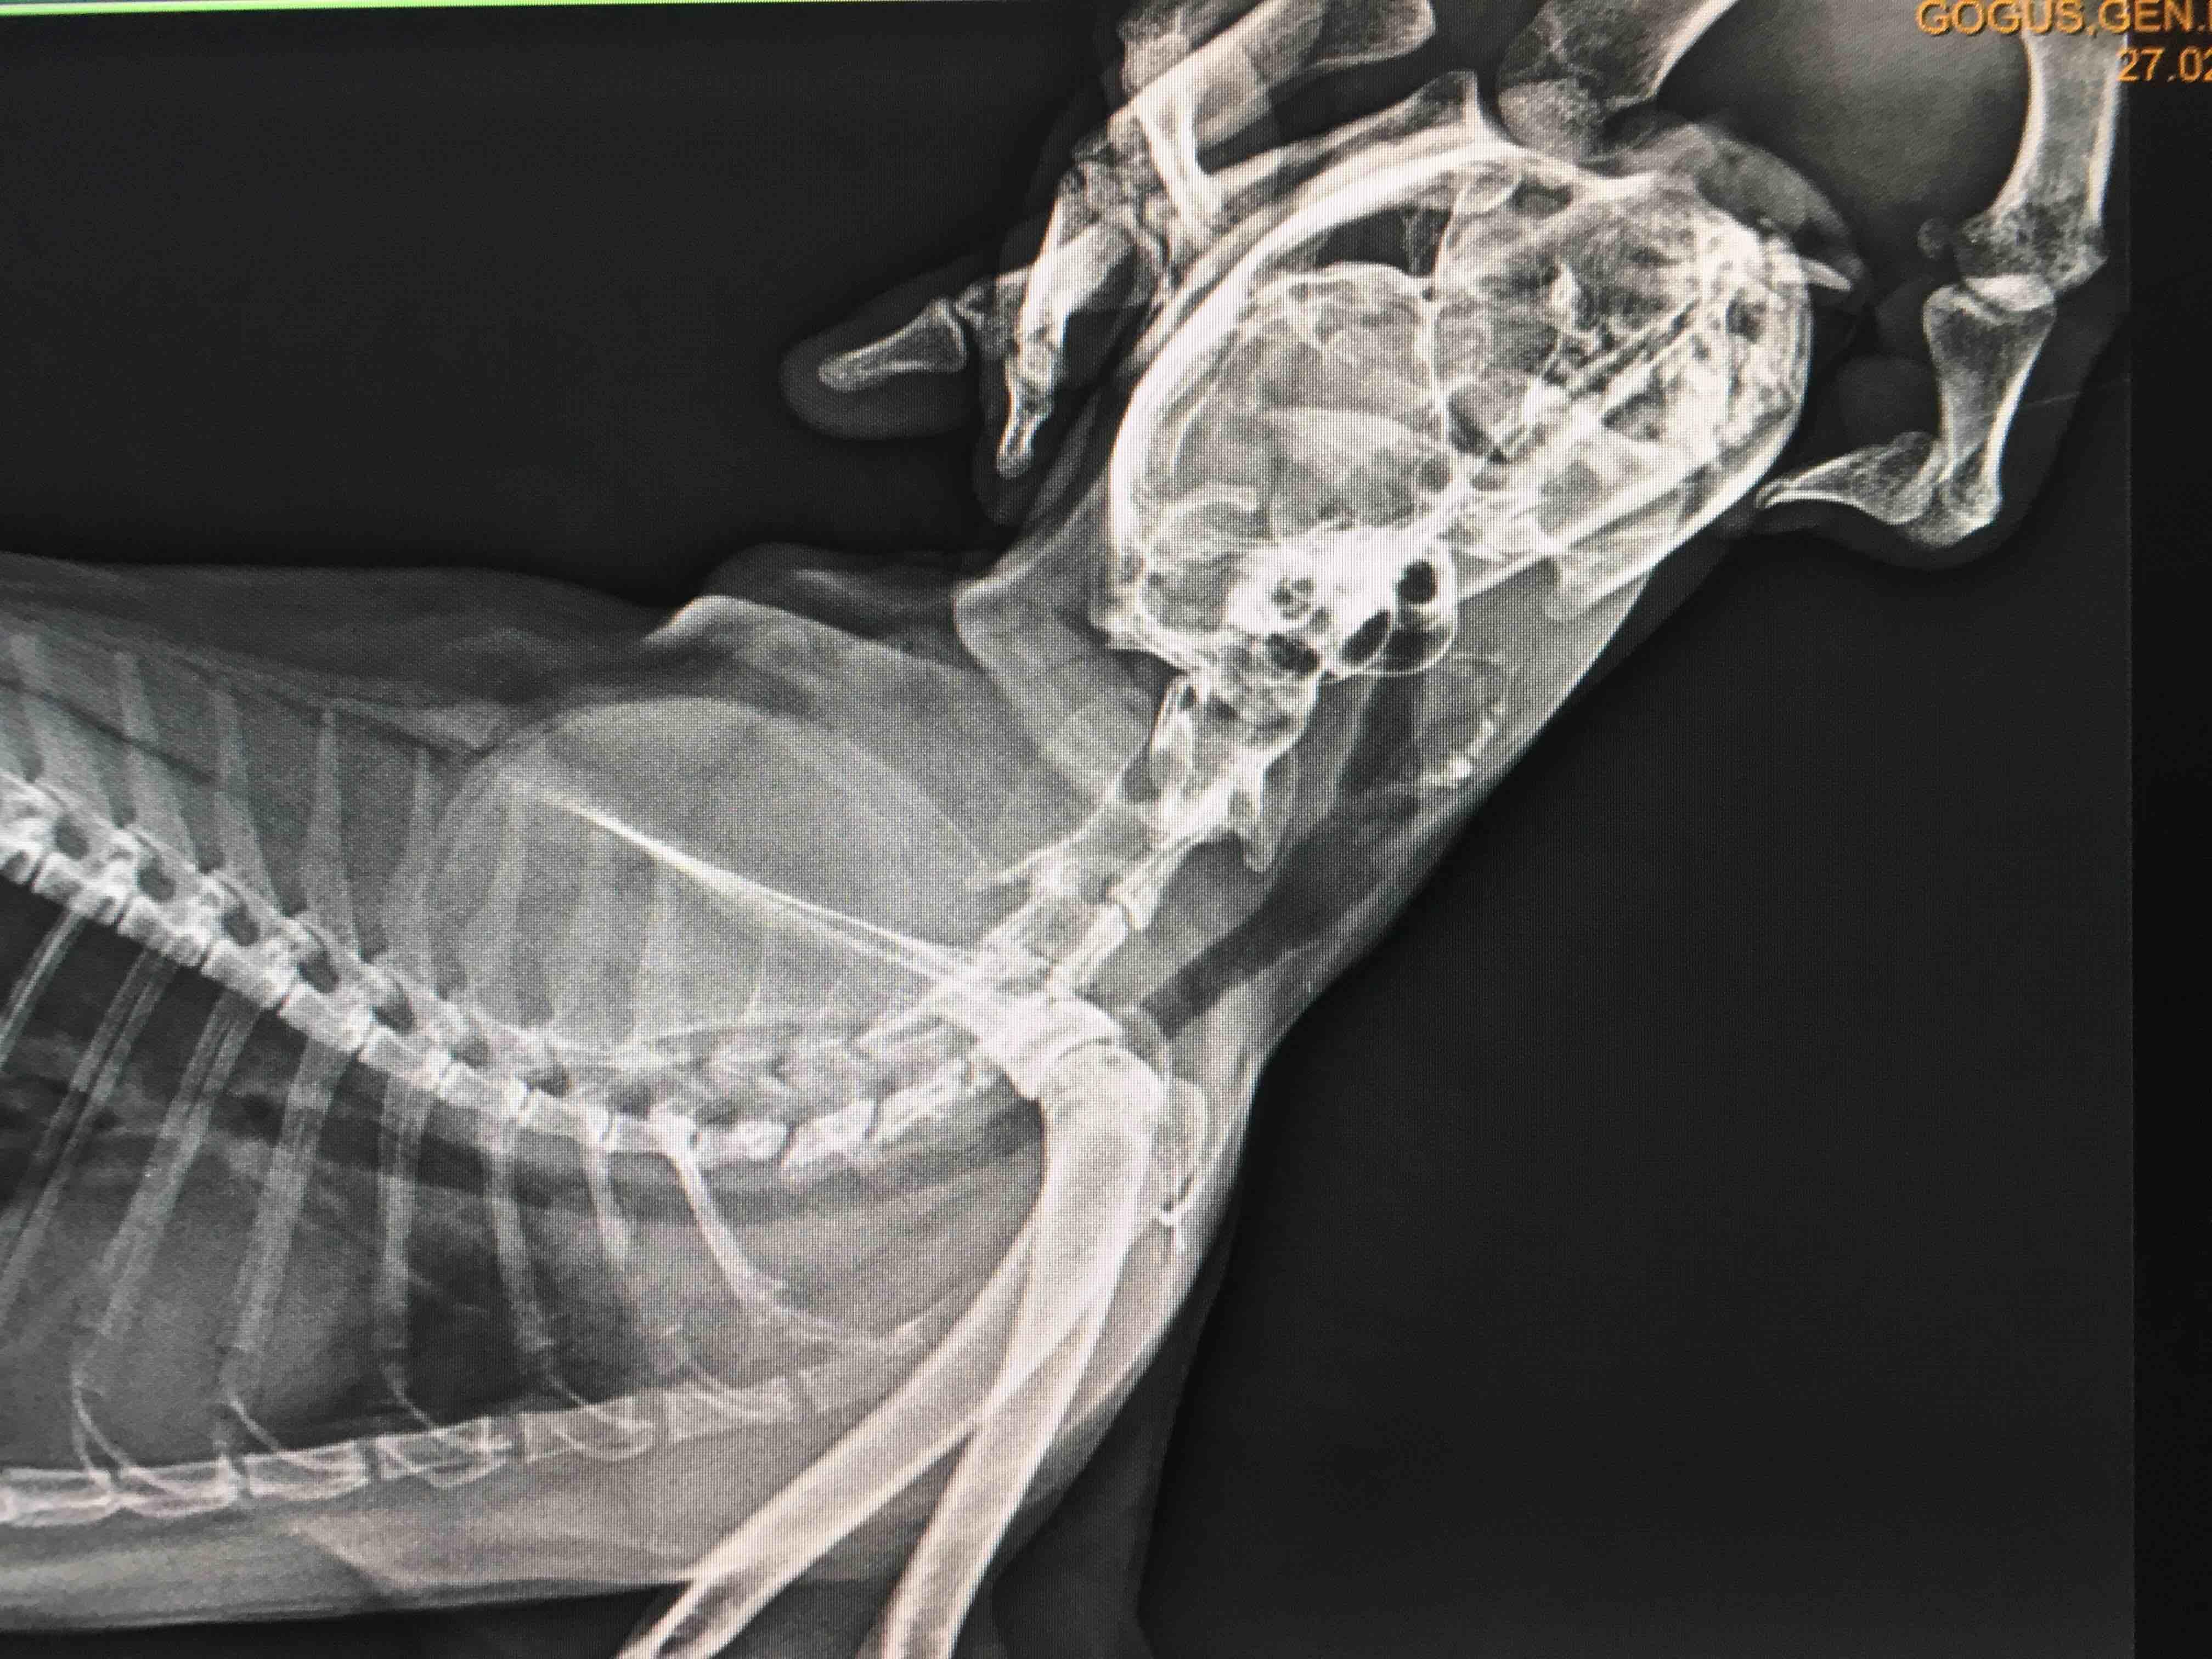

What is wrong with my cat’s esophagus?Veterinarian said it is not too bad but we have to check the condition every 2 months.Sometimes she vomits after eating.How high her water and food bowl must it be from the floor?Finally,can she eat from the floor level as it used to be?What can you advise for her condition?

Your vet has likely diagnosed megaoesophagus in your cat. There is no cure for this condition but it can be managed. Food should be fed from an elevation to allow gravity to help with swallowing. Sometimes a liquid diet is easier to swallow. It is important to monitor the lungs as aspiration pneumonia can easily develop which would require antibiotics. Finally sometimes drugs such as meyoclopramide which increase motility can be useful, but I would consult your vet regarding this.